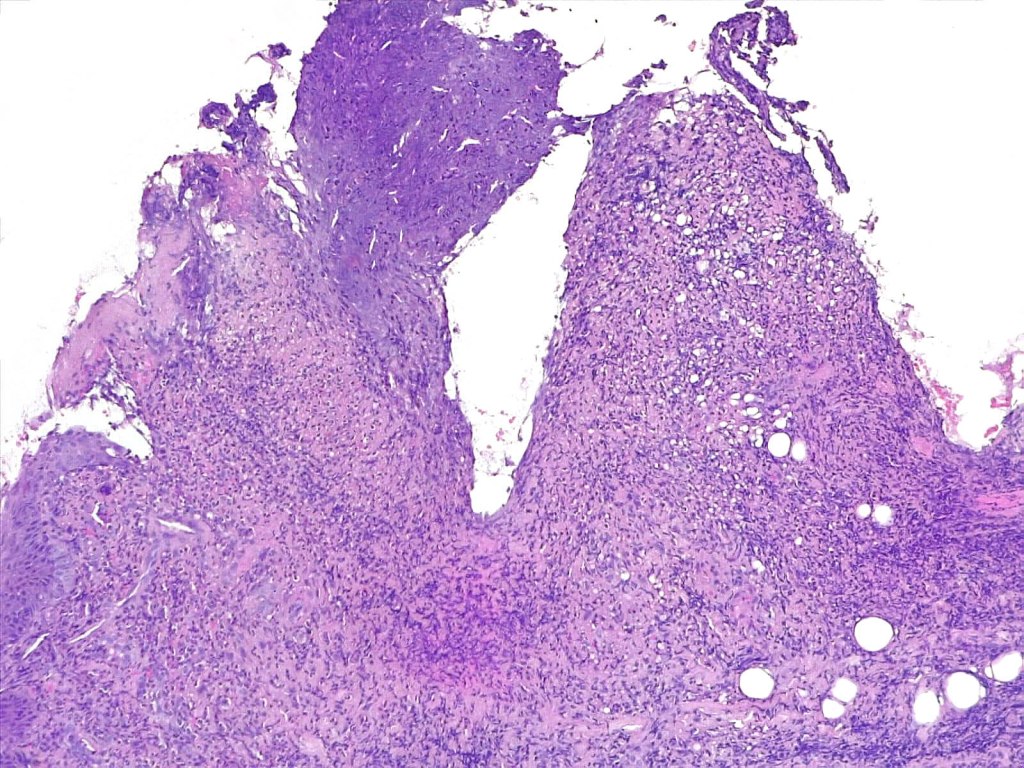

•Variable ulceration & Pseudoepitheliomatous hyperplasia

•Dense nodular or diffuse infiltrate of small to large atypical lymphocytes

•Angiotropism, angiodestruction, thrombi & coagulative necrosis